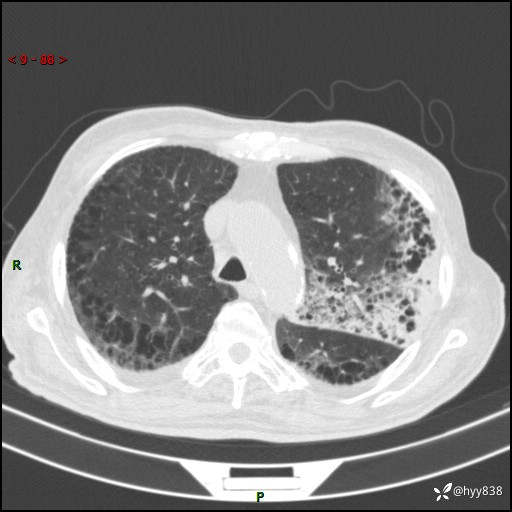

老年男性,间断咳嗽咳痰20余年,加重伴发热1天。呼吸科疑难病例讨论---结果公布

主诉:间断咳嗽咳痰20余年,加重伴发热1天

简要病史:家属代诉患者于20余年前无明显诱因出现咳嗽咳痰,痰为白色泡沫状,未行特殊治疗,不伴胸痛、胸闷、气喘、咳血等不适,1天前上午患者无明显出现发热,查体温39℃,伴咳嗽,咳痰无力,自行予以物理降温对症治疗,今晨2点左右再次出现发热,体温达40℃,自行服用复方氨酚烷胺对症治疗,凌晨3点左右复测体温38.2℃,现患者为求进一步诊治于今日就诊于我院门诊,行胸部CT提示双肺感染,遂以“肺部感染”收入我科。 患者本次起病来精神、食欲、睡眠欠佳,体力下降,体重无明显变化。

辅助检查:CT

胸部CT平扫